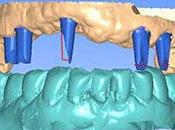

Cas clinique iTero (Cadent/Strauman) : reconstitutions unitaires multiples.

La CFAO Dentaire (Confection et Fabrication Assistée par Ordinateur) avec empreinte optique au cabinet dentaire permet de réaliser des reconstitutions... Lire la suite

Prothèses fixées sur implant à l'heure du numérique

Dans le cadre d'une réhabilitation orale implantaire, la finalité de notre traitement est la prothèse qui est placée sur les implants. Lire la suite

CFAO Restaurations temporaires non invasives avec un polymère haute performance

Grâce aux procédés modernes de fabrication industrielle, nous disposons aujourd'hui de résines et de composites qui permettent de confectionner des restauration... Lire la suite